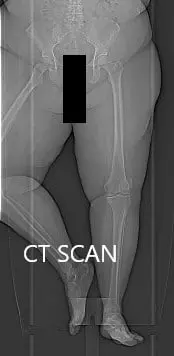

Topographic CT images of the weight-bearing Right and Left knee respectively.

A few weeks prior, a CT scan of the bilateral lower extremities was performed to obtain detailed data on the patient’s unique anatomy and biomechanics of the knees. A preoperative plan was formed to guide the surgeon in bone cuts and offsets. Disposable instruments were custom made for the patient. Unique customized implants were made to match the patients cut surface of the knee.